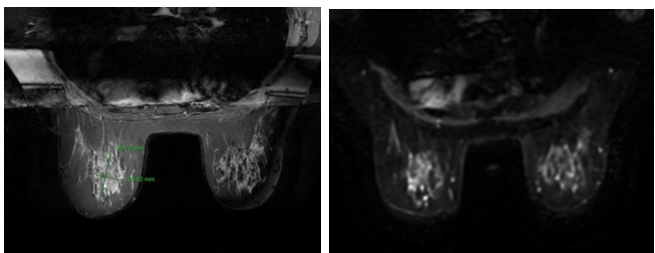

Sau 6 đợt truyền hoá chất phác đồ TCHP, bệnh nhân được làm các cận lâm sàng để đánh giá lại:

Chụp MRI đánh giá lại (4/2/2025) : Hiện không thấy tổn thương ngấm thuốc tuyến vú trái/ sau điều trị, đáp ứng hoàn toàn theo tiêu chuẩn RECIST 1.1.

Bệnh nhân có khối u vú trái kích thước ban đầu là 38x42cm, sau điều trị phác đồ TCHP 6 chu kỳ, khối u mục tiêu đã biến mất trên chẩn đoán hình ảnh, lâm sàng không sờ thấy khối u